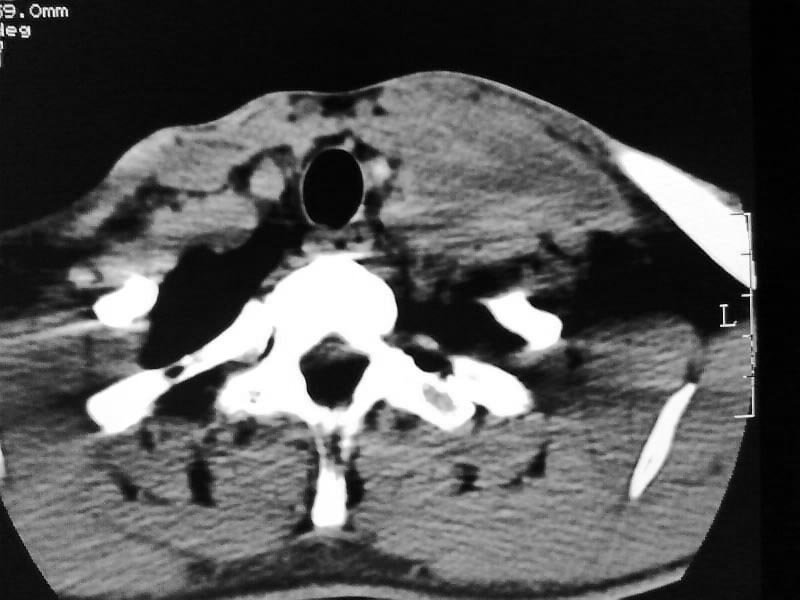

以下是引用余辉在2009-5-3 11:36:00的发言:[br]左侧胸锁乳突肌下方不规则肿物影,边界不清,内部密度不均,左侧颈外侧区脂肪增多,多发淋巴结肿大,考虑淋巴或神经来源肿瘤可能性大,不除外淋巴结炎,肌源性肿瘤及增生性肌炎等,活检